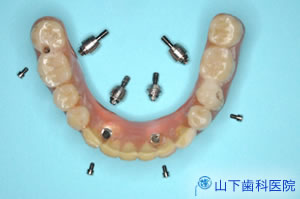

| そこであえて無用なCT撮影は行わず、触れて顎骨形態の特徴を細かく把握し、通常の石膏模型、通常のレントゲン画像を参考に、総入れ歯を透明レジンに置き換えて複製したものを石膏模型上で改造、ガイドのずれを止める固定用アンカーピンはノーベルガイドのものを利用する写真のようなインプラント埋入用自家製ガイドを作りました。 | ![]() |

![]() |

| 4本の長いブローネマルクインプラントを埋入、縫合した直後の状態です。 骨が軟らかく、上の歯が咬みこんで起こる微小動揺によって、互いに強固のつなぎ止めても、全体がゆさぶられるて骨結合しないリスクが高いと判断、即時負荷は避けました。 切開縫合した創が閉じて、しっかりした粘膜で覆われるまでの期間、入れ歯の底を削って軟らかい裏打ち材料(ティッシューコンディショナー)を貼り、硬くなってきたら貼り替えます。 |